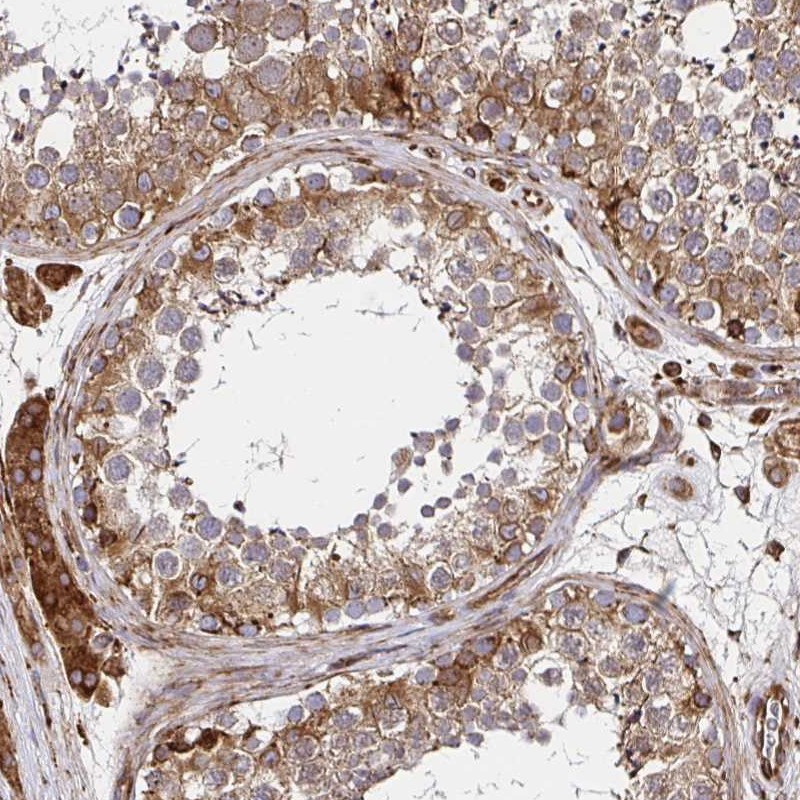

Immunohistochemical staining of human testis shows moderate cytoplasmic positivity in cells in seminiferous ducts, Leydig cells were strongly stained.